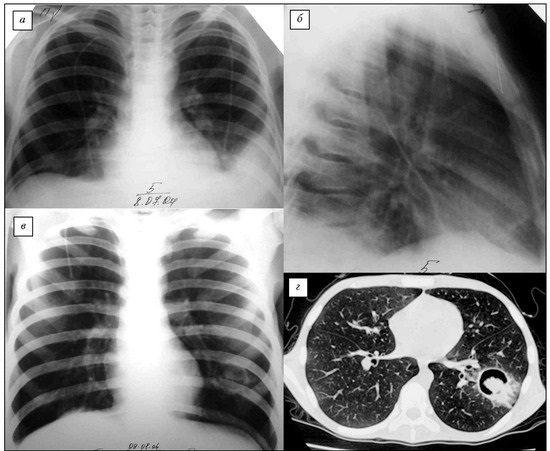

Визуализация и диагностика неинвазивного аспергиллеза с помощью КТ

Раздел: Необычные решения